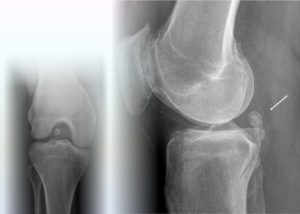

При рентгенографическом исследовании выявляются только хотя бы частично кальцифицированные свободные тела. Свободные тела, полностью состоящие из хряща, встречаются наиболее часто и совершенно неразличимы на рентгенограммах.

Во всех случаях необходимо выполнить рентгенографию в двух проекциях. Для чёткой оценки межмыщелковой вырезки рекомендовано исследование в проекции Розенберга (переднезадняя проекция в положении сгибания в коленном суставе на 45°).

Другим вариантом для этих целей является туннельная проекция Фрика. В некоторых случаях необходимы дополнительные косые (30°, 45°) или функциональные проекции. Проекция с максимальным сгибанием в коленном суставе обеспечивает наиболее чёткую картину передней межмыщелковой области для подтверждения или исключения наличия свободных тел, оссификатов или краевых остеофитов.

При оценке рентгенограмм могут возникать ошибки, причиной которых наиболее часто являются:

Нередко встречающаяся мелкая сесамовидная кость, локализующаяся в области прикрепления латеральной головки двуглавой мышцы. При выраженных случаях остеоартроза, фабелла может определяться на рентгенограммах как образование неправильной формы с нечёткими контурами.

- Медиальная фасетка надколенника.

При рентгенографии, выполняемой после вывиха надколенника с разрывом медиального ретинакулюма, могут появляться участки оссификации и кальцификации ретинакулюма.

При тангенциальных проекциях они приобретают округлый вид, что позволяет заподозрить интраартикулярные свободные тела.

Однако во время артроскопии в этой области свободные тела практически никогда не обнаруживаются, поскольку оссификаты и кальцинаты почти всегда располагаются подкожно и недоступно для артроскопии.

- Рентгенограмму коленной области;

- Компьютерную томограмму.

Они наглядно демонстрируют дополнительное плотное образование, не связанное с какими-либо суставными структурами. Если это образование не выявляется во время рентгенограммы, выполняют снимок с контрастированием воздухом (пневмоартрография) или двойным контрастированием (контрастное вещество и воздух).